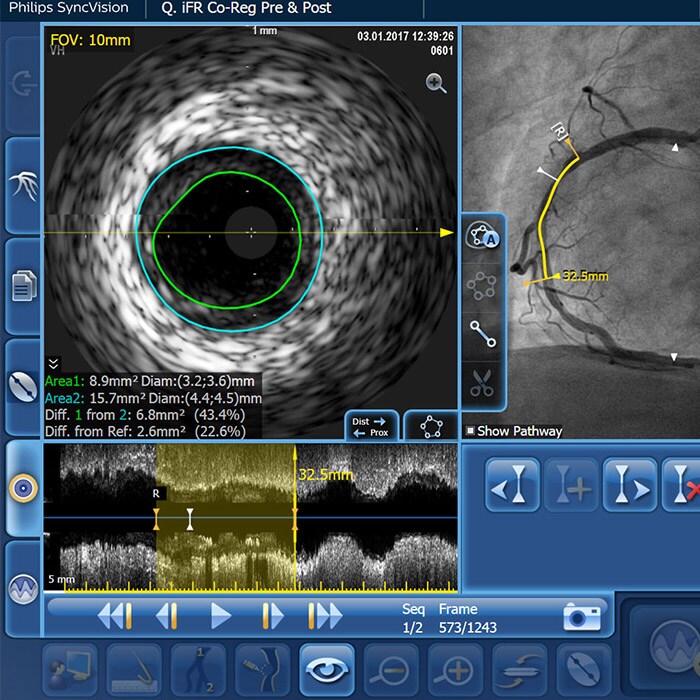

An increasing number of patients with calcified coronary artery lesions are being referred for PCI. A recent pooled analysis reported moderate to severe target lesion calcification in 32% of patients.1